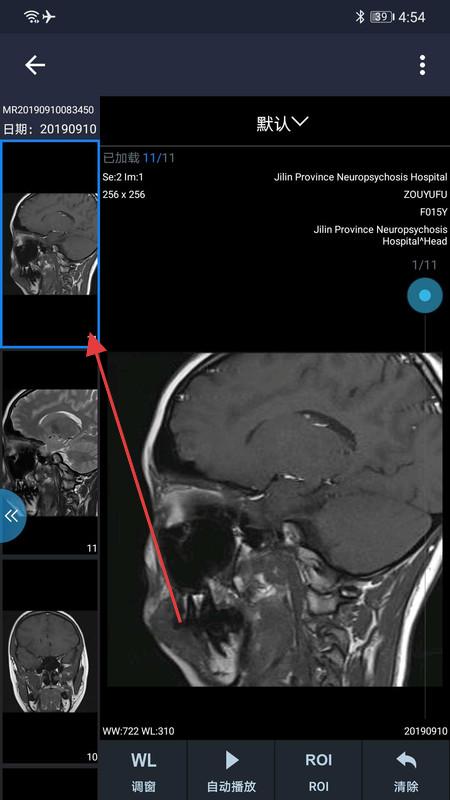

1、打开和缓医疗APP,进入影像查看页,点击左侧影像缩略图,可切换显示不同部位影像,配合下方功能键,辅助分析诊断。